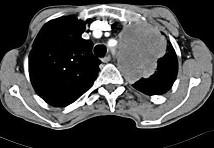

问题 56岁,男,意识错乱情绪不稳定1周,请结合胸片和CT图,选出最可能的诊断 ( )

选项 A.肺癌 B.错构瘤 C.胸内甲状腺肿 D.韦格肉芽肿 E.胸腺瘤

答案 A